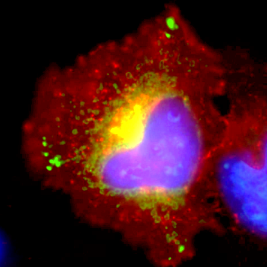

HeLa cell expressing malaria ARF fused to GFP